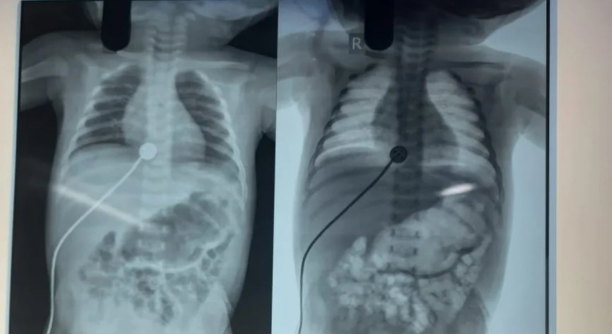

Abdominal X-rays (showing dilated bowel loops)

Meconium Ileus is a bowel obstruction in newborns caused by thick, sticky meconium (the baby’s first stool) blocking the small intestine, typically the ileum. It is often the first sign of cystic fibrosis (CF) and requires prompt treatment to avoid complications like bowel perforation or infection.